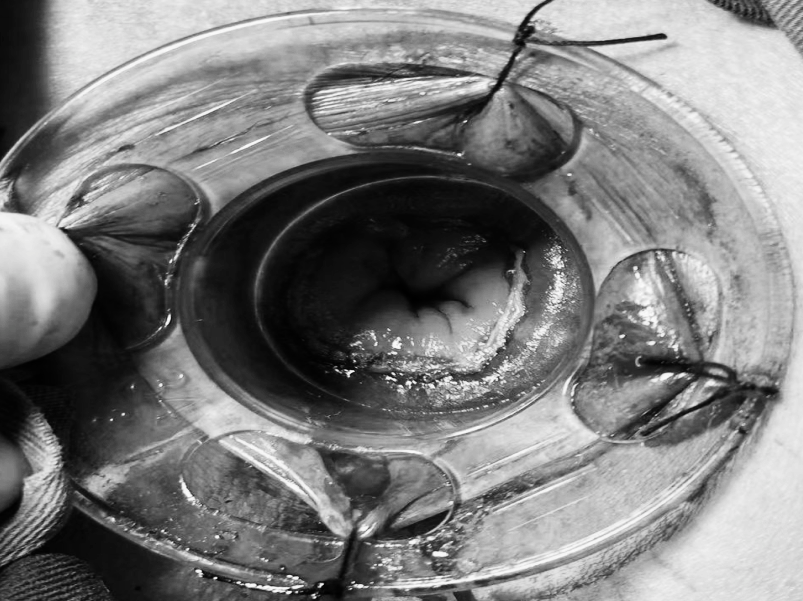

为深入践行人才强院核心战略,加速打造高水平医疗专家团队,引领学科跨越式发展,7月15日,贵州航天医院成功签约(柔性引进)知名肛肠外科专家高大勇教授,并举行“高大勇教授名医工作室”授牌仪式。贵州航天医院党委书记杨军,院长廖江荣,副院长彭亮、马庆庆、蒋婷出席仪式,普外科全体医护人员参加。 仪式上,杨军为高教授颁发了聘书,双方共同签署了合作协议,高教授授予普外科“名医工作室”函牌。 聘书颁发 柔性人才引进协议签约 名医工作室授牌 仪式后,高大勇教授前往科室开展早交班、教学查房等工作,针对疑难病例给予专业的治疗建议和科学指导。 此次柔性引进高大勇教授并设立名医工作室,将进一步促进贵州航天医院普外科在学科建设、技术创新、人才培养、科研教学等方面能力的提升,推动我院肛肠疾病诊疗能力实现跨越式发展,为广大患者带来优质医疗服务。 贵州航天医院普外科专家团队 高大勇 普外科(肛肠外科)学科带头人、名誉主任,主任医师、教授 临床擅长:对中西医结合诊治肛肠学科各种常见病、多发病及疑难杂症等具有丰富的临床经验。 原遵义市第一人民医院(遵义医科大学第三附属医院)、遵义市中医院肛肠科主任。中华中医药学会肛肠分会常委,全国中医肛肠学科名专家,中国健康促进与教育协会肛肠分会常委,中国康复医学会肛肠疾病康复专业委员会常委,中国民间中医医药研究开发协会肛肠分会副秘书长,中国医师协会中西医结合肛肠医师专业委员会常委,国家二级心理咨询师,贵州省第一批中医名医工作指导老师,遵义市名中医,遵义市肛肠学会会长,遵义市肛肠质控中心名誉主任,遵义市中西医结合学会名誉会长,遵义市健康科普专家,原贵州省中西医结合学会肛肠分会副主任委员、贵州省中医肛肠质控中心副主任、遵义市医学会医疗鉴定委员会专家、遵义市卫生系列高评委。发表论文30余篇,主编和参编医学著作5本,主持省级科研课题2项、市级科研课题2项、院级科研课题1项。 梁 跃 中共党员,普外科党支部书记、主任,主任医师 临床擅长:对普外科各类肿瘤手术具有丰富的临床经验。 毕业于遵义医学院,遵义市医学会小儿外科学分会常务委员,遵义市肛肠协会理事,遵义市医学会核医学分会(第二届)委员会委员;荣获第三期“黔医人才计划”优秀学员称号;主持市级课题1项,完成省级课题1项,在国内各类刊物上发表论文10余篇。 钱科洪 民盟盟员,普外科副主任医师 临床擅长:从事普外科临床工作30余年,对各类普外科疾病的诊治,乳腺、甲状腺、胃十二指肠、结直肠等疾病及疑难杂症诊治具有丰富的临床经验。 毕业于遵义医学院临床医疗系,2009年前往中山大学附属第一医院微创外科进修学习,在国内各专业期刊发表论文数篇。 贵州航天医院普外科简介 基本情况 贵州航天医院普外科成立于1968年,前身属于航天部O61基地3417医院外一科,1998年3417医院、3427医院合并后更名为普外科,下设胃肠外科、肛肠外科2个亚专业科室,拥有在全市较为先进的专科设备和技术,是中国疝病专科联盟单位,贵州医科大学附属医院胃肠外科专科联盟单位。开放床位40张,配备医护人员21人。 专科特色 普外科致力于胃肠及肛肠疾病的外科临床诊治及科研,以腹腔镜微创外科技术为本,形成以快速康复治疗胃肿瘤、结直肠肿瘤、小肠肿瘤、直肠脱垂、肥胖病、急腹症、各类疝、痔、瘘等专科特色,同时注重胃肠疾病尤其是结直肠恶性肿瘤的基础研究和临床转化研究,总体诊断和治疗水平在区域同级医院居于领先水平。 开展手术:腹腔镜下胃癌根治术,腹腔镜下袖状胃切除术,腹腔镜下胃肠道间质瘤切除术,腹腔镜下结、直肠癌根治术,胃癌、结直肠癌的精准治疗,腹腔镜下小儿疝气、成人疝修补术,腹腔镜下阑尾手术,内痔的硬化注射治疗及痔疮的微创治疗:ATH、PPH、TST,直肠脱垂的各种手术治疗,难治性伤口VSD技术,鼻胃肠管、肠梗阻导管置入术,肛肠术后间歇性导尿技术,并引进了中医适宜技术,也为各种化疗患者提供输液港安装,提高患者就医体验。 腹腔镜下腹股沟 疝无张力 修补术 腹股沟疝里金 斯坦(Lichten stein)手术 PPH微创术治疗环状混合痔 黏连性或炎性肠梗阻-肠梗阻导管 腹腔镜袖状胃切除 腹腔镜阑尾切除术 腹腔镜阑尾肿瘤切除术 腹腔镜下结肠癌根治术 诊疗范围 胃肿瘤、结直肠肿瘤、小肠肿瘤、肥胖症、各类急腹症、腹部外伤、腹壁疝、便秘、直肠脱垂、痔疮、肛瘘、肛裂等胃肠、肛肠外科疾病。 END